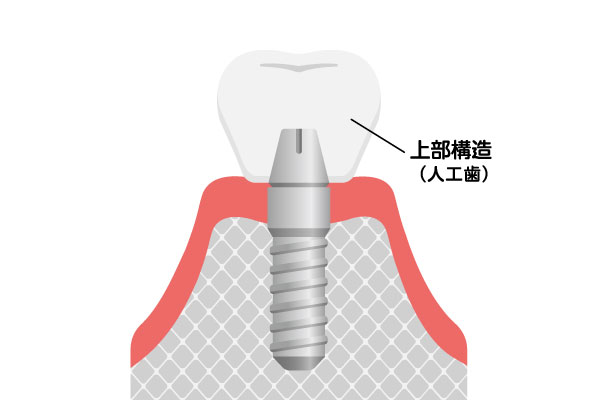

上部構造(人工歯)

ジルコニア

オールセラミック

被せ物の装着

型採りを行い、精密な被せ物を作製して装着します。周辺の歯との色味の調和はもちろん、かみ合わせのバランスを微調整し、自分の歯のように違和感なく噛める状態に仕上げます。